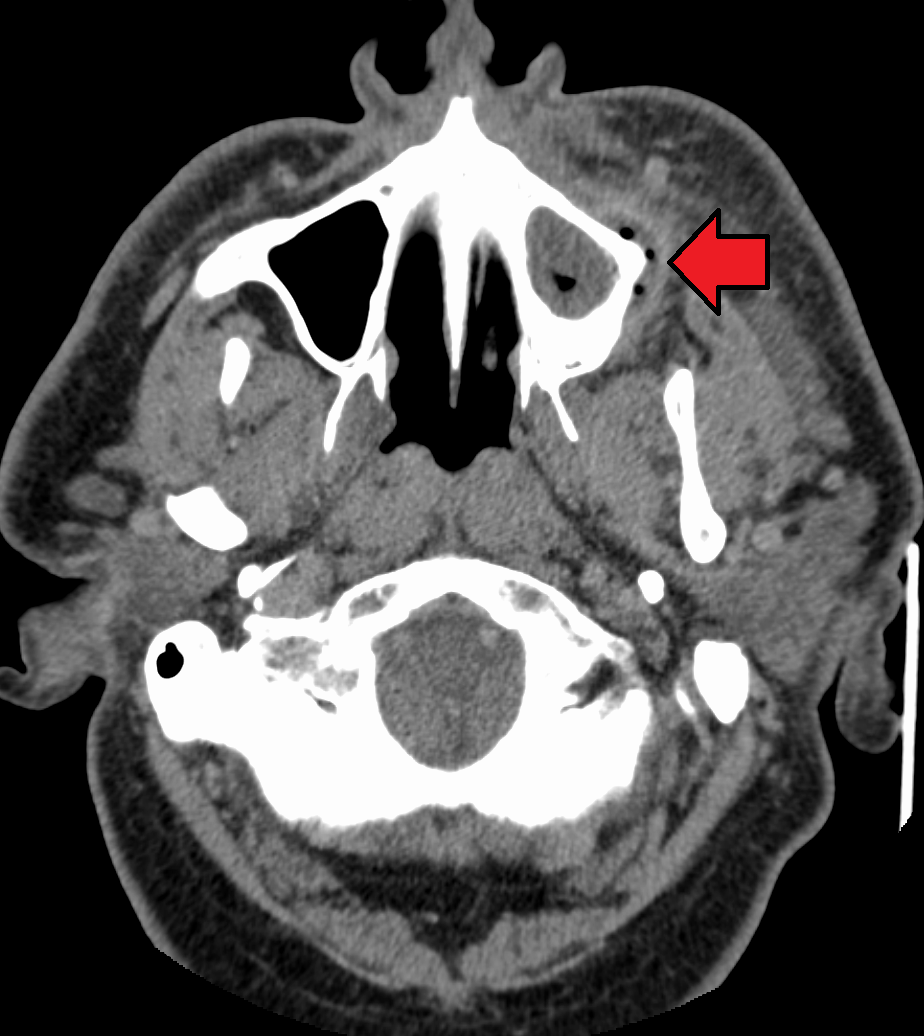

치아 농양을 치료하지 않고 방치하면 뼈를 관통하고 연조직으로 확장될 정도로 커져 골수염 및 봉와직염으로 진행될 수 있다. 거기에서 감염은 최소 저항 경로를 따라 내부 또는 외부로 퍼질 수 있다. 감염 경로는 감염된 치아의 위치, 뼈, 근육 및 근막 부착 부위의 두께와 같은 요인의 영향을 받는다.

내부 배농은 성장하는 감염이 감염 주변 조직 내에서 공간을 만들기 때문에 더 우려된다. 즉시 입원이 필요한 심각한 합병증으로는 성장하는 감염과 봉와직염의 조합인 루트비히 협심증이 있으며, 이는 극단적인 경우 기도를 닫아 질식을 유발할 수 있다. 또한 감염은 조직 공간을 따라 종격동으로 퍼져 심장과 같은 생명 유지 기관에 심각한 영향을 미칠 수 있다. 또 다른 합병증은 일반적으로 위쪽 치아에서 발생하며, 패혈증이 경로를 통해 이동하여 심내막염, 뇌 농양 (극히 드물게), 또는 수막염 (또한 드물게)으로 이어질 수 있는 위험이 있다.